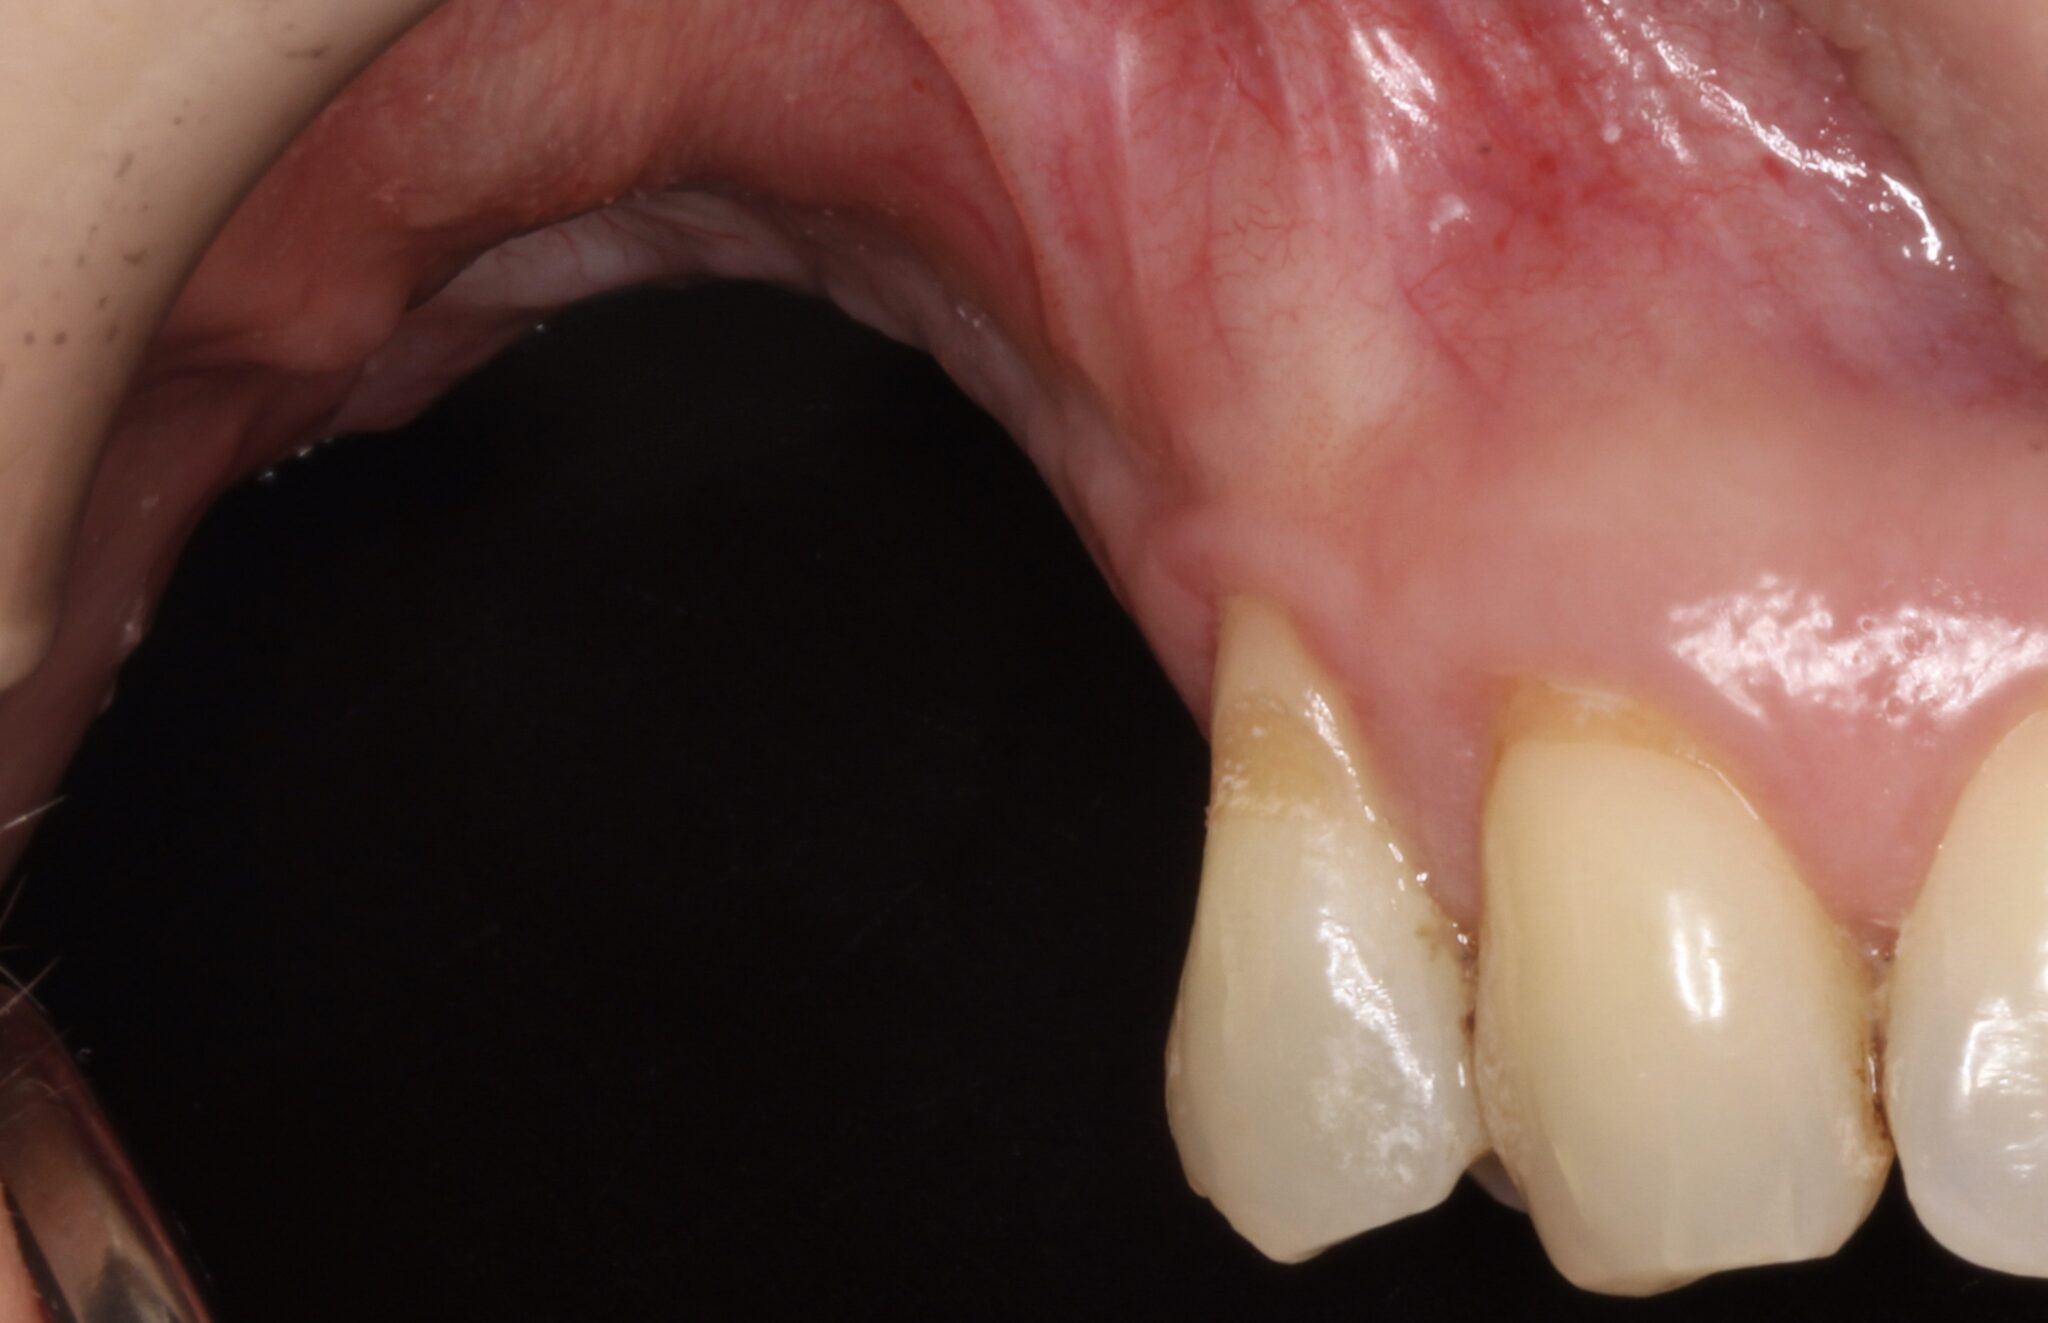

Figure 20.

2 months later it was evident that there was no keratinised mucosa at buccal aspect and in fact even on the supracrestal area lack of keratinised mucosa was observed.